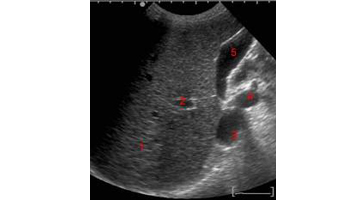

- Abdominale

- Abdomino-pelvienne.

- Vessie, reins, prostate.